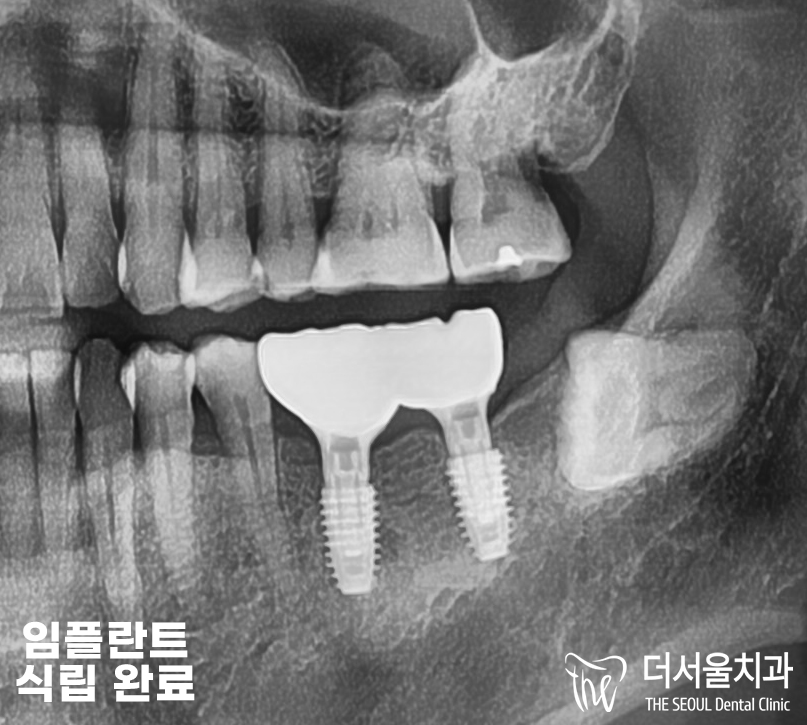

『결과』

모란역치과에서 수술이 끝났을 때,

파노라마 엑스레이 촬영으로

식립 된 임플란트를 보여드리고 있습니다.

픽스처와 뼈 사이에 틈이 없이

잘 채워진 것을 찾아볼 수 있죠?

저렇게 골 결합이 잘 이뤄져야

고정이 되어 튼튼히 사용할 수 있습니다.